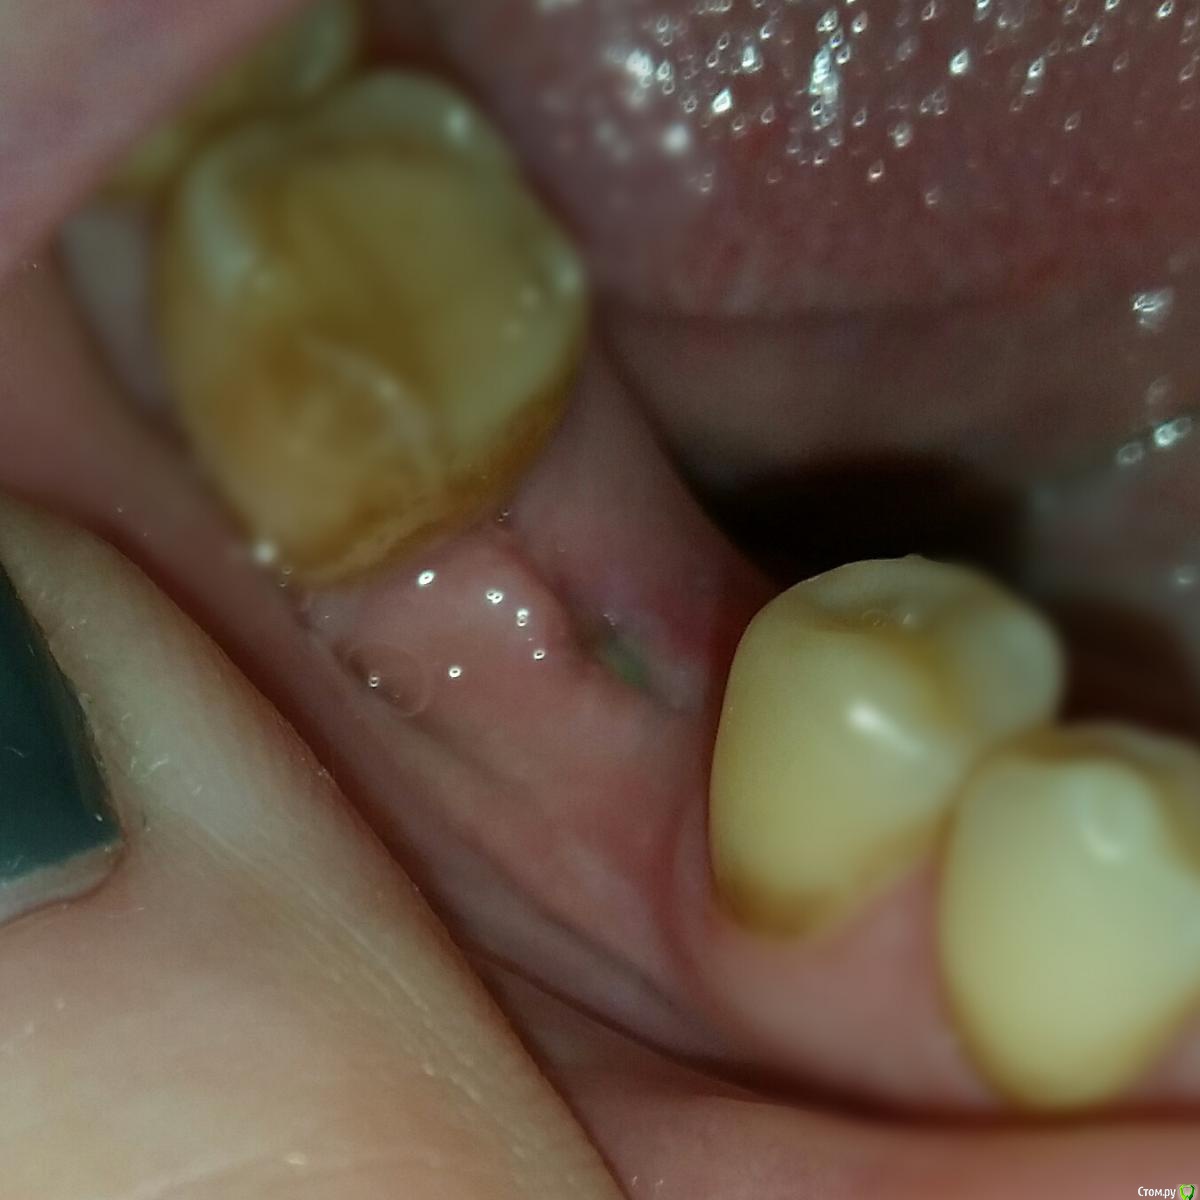

Валерия2020 Опубликовано 9 декабря, 2016 Автор Поделиться Опубликовано 9 декабря, 2016 (изменено) Посмотрите, пожалуйста, апдейт. Фото десны спустя неделю лечения солкосерилом и хлоргексидином.Всё-таки ставить формирователь или ждать положенные 3 месяца?Спасибо Изменено 9 декабря, 2016 пользователем Валерия2020 Ссылка на комментарий

Romanson Опубликовано 10 декабря, 2016 Поделиться Опубликовано 10 декабря, 2016 По последнему фото вроде нормально всё. Ссылка на комментарий

red_butler Опубликовано 11 декабря, 2016 Поделиться Опубликовано 11 декабря, 2016 Так уже лучше, но на раскрытии с десной нужно будет поработать. 2 Ссылка на комментарий